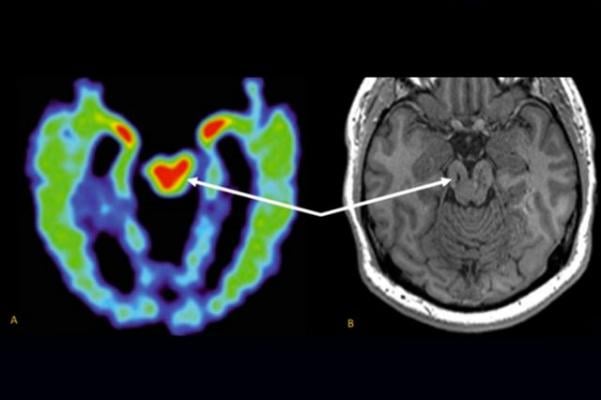

The pet scanner will detect the tracer and turn the data into 3 d images on a computer monitor. During the scan a narrow x ray beam circles your body taking a series of images from different angles. Pet scans provide metabolic information and are increasingly read alongside ct or mri magnetic resonance imaging scans which provide anatomic information. Learn about their similarities and differences here.

What is a ct scan. Mri or magnetic resonance imaging uses strong magnetic fields and radio waves to make images of the organs cartilage tendons and other soft tissues of the body. Pet scans and ct scans are both critical diagnostic tools that provide clear accurate views into the body. Pet scans positron emission tomography scans are often done in conjunction with ct scans computerized tomography scans or mri scans magnetic resonance imaging scans.

While it sounds scary the tracer typically leaves your body a few hours after the scan. Pet scan compared to a ct scan. Positron emission tomography pet scans measure emissions from positron emitting molecules. A pet scan uses small amounts of radioactive substances called contrast materials for contrast within the body.